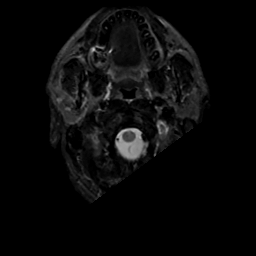

MR Study #10, April 28, 1991 -- Slice #1